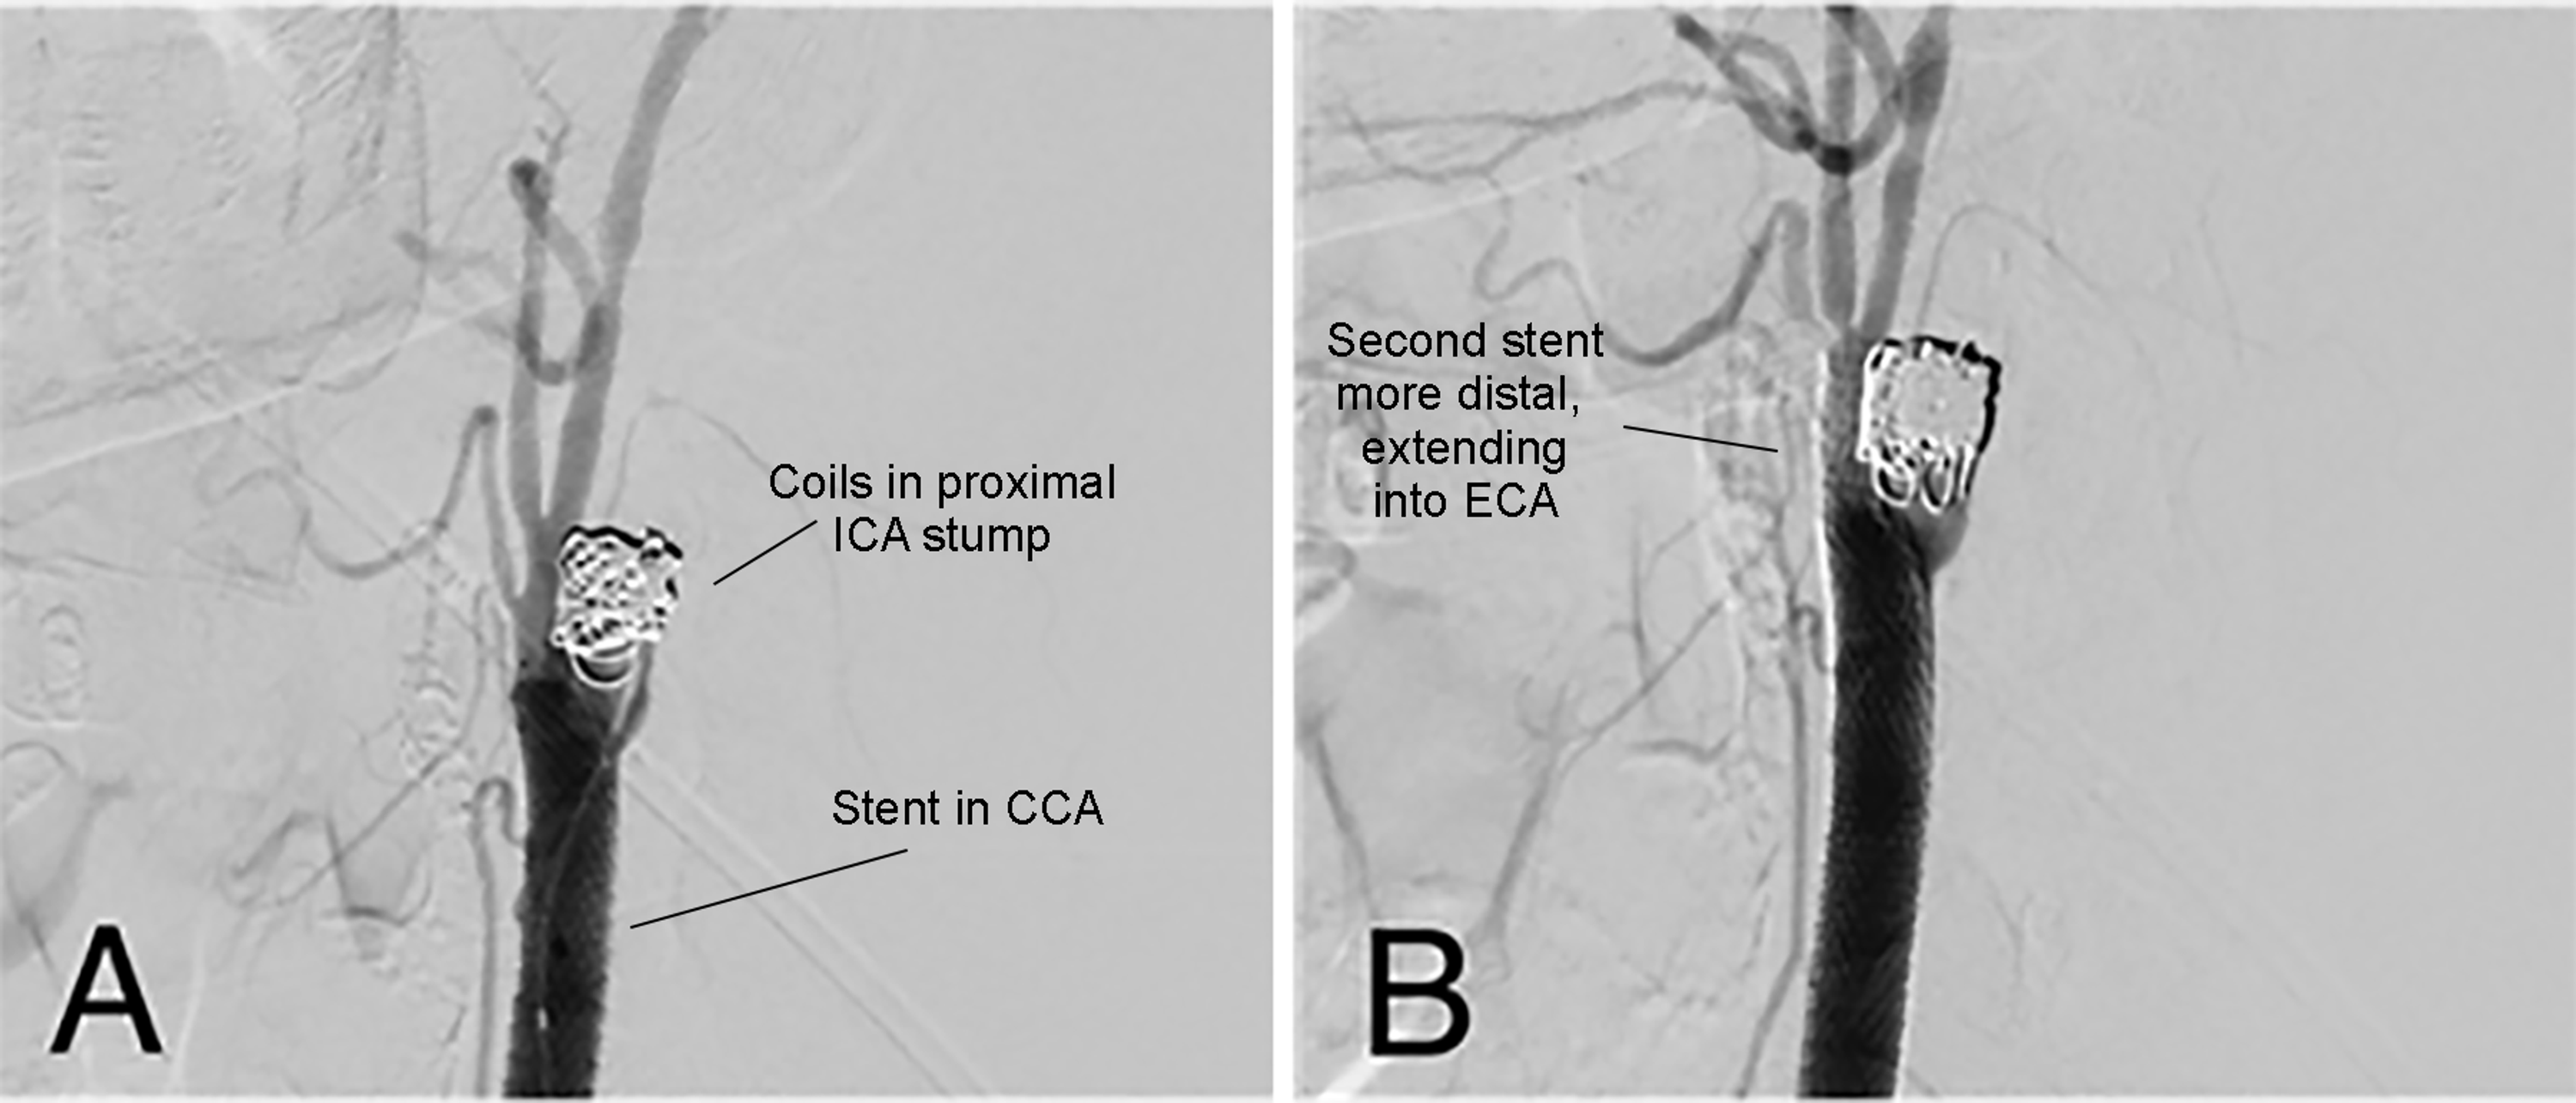

From www.cureus.com

Carotid Stump Syndrome With StentAssisted Coil Embolization Cureus Coil Embolization Post Stroke the aim of this study was to identify predictors of ischemic stroke after intraprocedural thrombosis after stent. like all procedures involving the blood vessels of the brain, a coil embolisation carries a small risk of stroke. an aneurysm coil is a device inserted via catheter to fill in a brain aneurysm — a bulge in a blood. Coil Embolization Post Stroke.

Permanent coil embolization of the proximal external carotid artery Coil Embolization Post Stroke an aneurysm coil is a device inserted via catheter to fill in a brain aneurysm — a bulge in a blood vessel. like all procedures involving the blood vessels of the brain, a coil embolisation carries a small risk of stroke. endovascular coil embolization is a percutaneous approach to treat an intracranial aneurysm from within the. A. Coil Embolization Post Stroke.